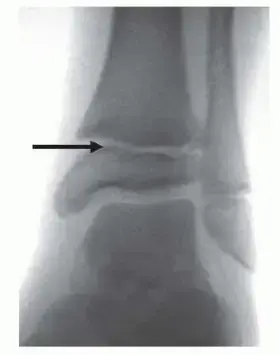

تصنيف كسور الكاحل عند الأطفال (تصنيف سالتر-هاريس)

لتحديد خطة العلاج المثلى، يعتمد الأستاذ الدكتور محمد هطيف على التصنيف العالمي لكسور صفائح النمو المعروف بـ "سالتر-هاريس" (Salter-Harris)، والذي يقسم الكسور إلى خمسة أنواع رئيسية:

1. النوع الأول (Type I): كسر يمر عبر صفيحة النمو فقط دون التأثير على العظم المحيط. غالباً لا يظهر بوضوح في الأشعة العادية ويحتاج لخبرة سريرية لتشخيصه.

2. النوع الثاني (Type II): الكسر الأكثر شيوعاً، يمر عبر صفيحة النمو ويصعد إلى جزء من جسم العظمة (Metaphysis).

3. النوع الثالث (Type III): كسر يمر عبر صفيحة النمو وينزل نحو المفصل (Epiphysis). يتطلب دقة شديدة في العلاج لضمان استواء سطح المفصل.

4. النوع الرابع (Type IV): كسر يقطع جسم العظمة، صفيحة النمو، ونهاية العظمة وصولاً للمفصل. يحتاج غالباً لتدخل جراحي دقيق.

5. النوع الخامس (Type V): إصابة نادرة ولكنها خطيرة جداً، تحدث نتيجة "انضغاط" أو هرس لصفيحة النمو. يصعب تشخيصها مبكراً وتؤدي غالباً إلى توقف نمو العظمة.

2. الأشعة السينية (X-rays): الإجراء الأساسي لرؤية العظام وتحديد نوع الكسر ومكانه. يتم أخذ صور من زوايا متعددة.